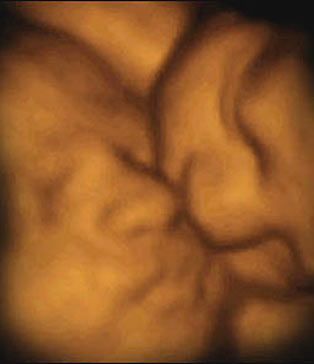

一对双胞胎姐妹中的一个斜靠在另一个身上,还亲了一下对方的脸——这个温馨的画面不是发生在某座大房子里,而是发生在妈妈的子宫里!在英国媒体日公布的一系列照片中,读者能够清晰地看到这些令人震惊的“四维”超声波图像,看到双胞胎和多胞胎是怎样在妈妈的子宫里“玩耍”的。

由于对胎儿进行的是实时拍摄,科学家把这些珍贵的图像称为“四维”图像,他们按照这些图像制作出真实大小的硅树脂模型,并用电脑制作出令人震惊的多胞胎图像。